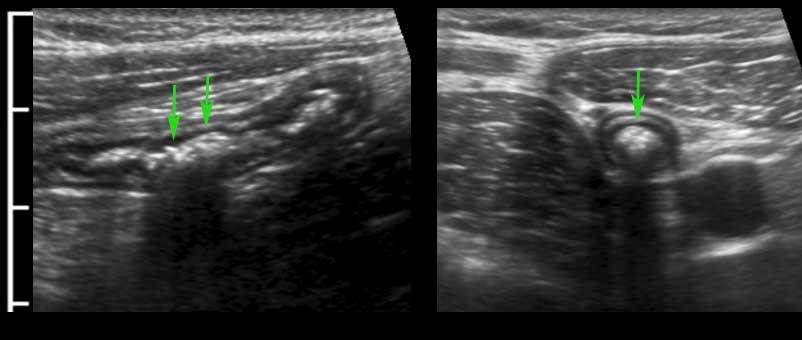

Hình ảnh dọc (trái) và ngang (phải) của đại tràng sigma rỗng ở bệnh nhân gầy.

Trong hình ảnh mặt cắt ngang, ba vùng dày lên cục bộ của lớp cơ (đầu mũi tên) đại diện cho ba dải cơ dọc kết tràng (đầu mũi tên).

Đại tràng bình thường chứa đầy phân (trái), trong quá trình co thắt (giữa) và trong quá trình giãn và nén (phải).

Normal colon wall thickness during compression is 3-4 mms.

Bóng lưng âm học của phân cản trở việc hiển thị siêu âm thành sau (bên trái).

Đại tràng được phân biệt với ruột non bởi vị trí, nội dung phân, nhu động thưa và lớp cơ ngoài dày với ba dải cơ dọc (tenia coli).